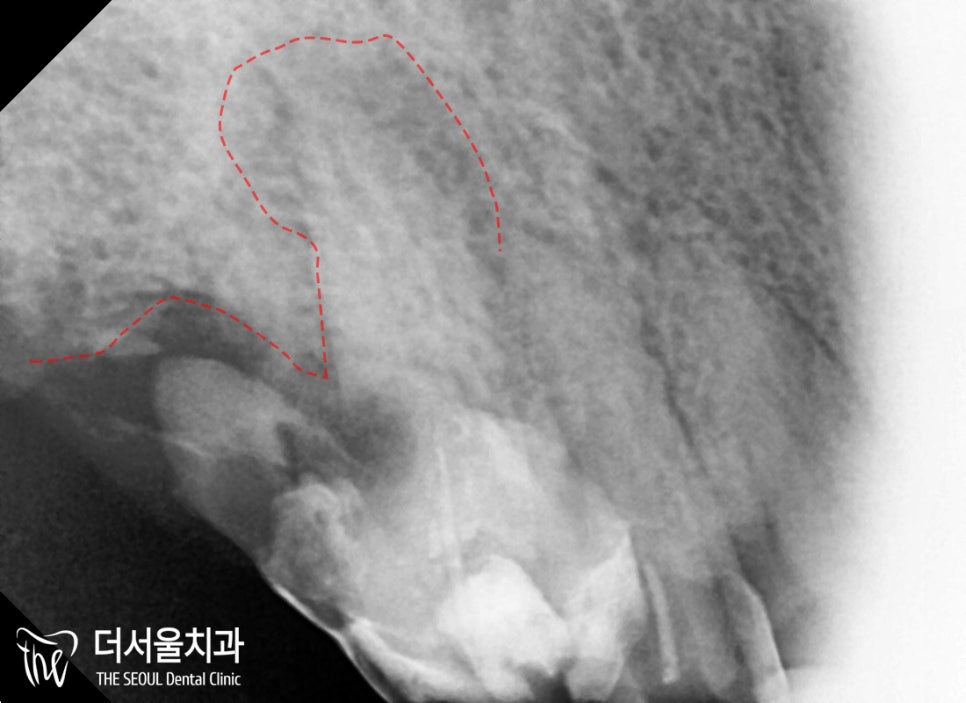

이전에

캔틸레버 브릿지라고 하여

한쪽에만 지대치를 둔 방식으로

보철을 씌워두신 것이 보였으며,

예상했던 대로 #14는

인접면 우식이 생겨있었습니다.

이미 보철 하방으로

치조골 소실도 심하고, 충치도 깊었기에